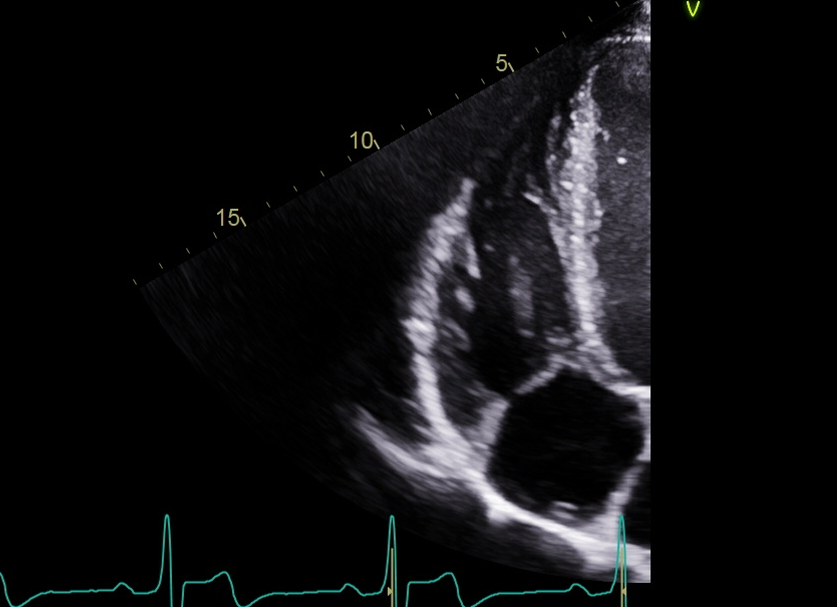

RA volume, measure when the chamber is at its largest, just right before the TV open, at end-systole

Trace the chamber excluding the TV annulus

and we also do a length

a normal RA size is going to be less than 19 centimeters squared